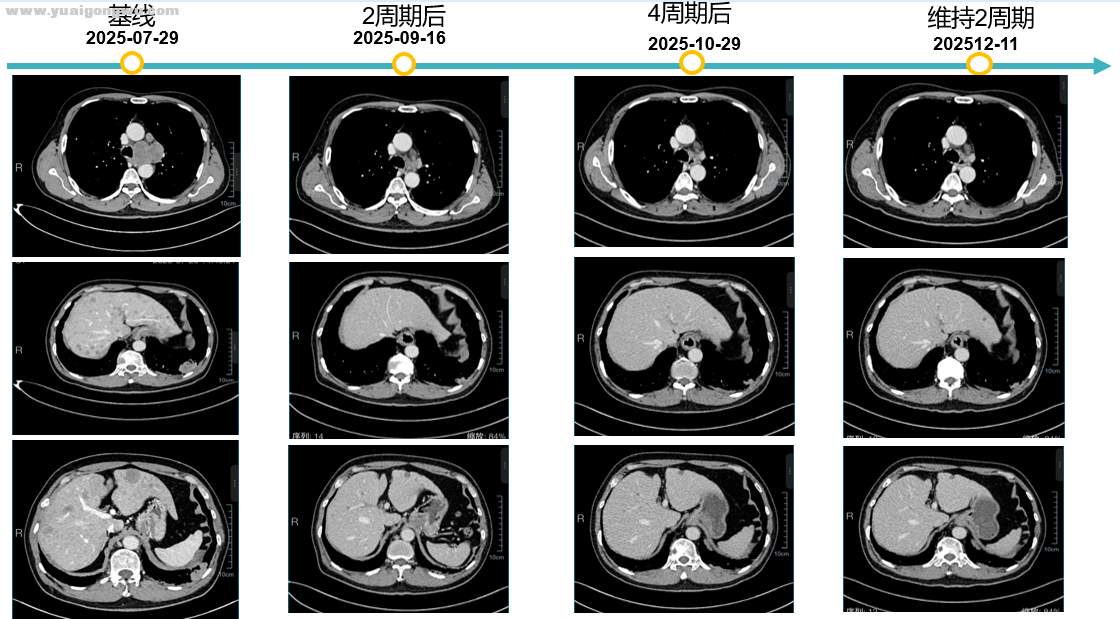

患者概况: 65岁男性,身高165cm,体重61kg,既往无基础病; 患者2025年7月就诊于湖南省直中医院,腹部增强CT(2025-7-28):肝实质内弥漫大小不等弱强化结节,考虑转移瘤可能性大。 2025年7月29颈胸增强CT:左下肺外基底段及左肺下叶前内基底段新见肿块,考虑恶性肿瘤(肺癌并肺内转移可能性大);左侧胸膜局部增厚不均匀强化:考虑转移;左锁骨上窝、纵隔及左肺门多发肿大淋巴结:转移性淋巴结可能性大;左侧第6后肋、胸椎及胸骨多发溶骨性骨质破坏:考虑骨转移瘤,右侧髂骨成骨性改变。肝实质内弥漫大小不等弱强化结节,考虑转移瘤可能性大;余双肺多发小结节,部分新见,转移待排,建议追踪复查。 2025年7月30日头部增强MRI:脑萎缩;颅内未见异常强化灶。 确诊为:左肺下叶小细胞癌(T2N3M1c IVB期),左肺门、纵隔及左侧锁骨上淋巴结转移、肝转移、骨转移; 其他诊断:慢性阻塞性肺疾病、双肺间质纤维化、左肾囊肿;

5 X$ {; s1 R, B: G治疗过程: 一线治疗:2025-8-5 至2025-11-25行EP方案+阿替利珠单抗治疗4周期,阿替利珠单抗维持治疗2周期,地舒单抗治疗骨转移; / s) X( Z0 h! Q: m5 H' k

一线治疗效果如下: 由于患者从后颈到前额阵发性头晕头痛,紧急入院检查核磁(2026年1月12日)。化放同时患者头晕、头痛、呕吐,进食少,输营养液。

李成海教授(影像科) 梳理患者全部影像资料如下:2025年7月份初始胸部CT提示,左下叶有两个病灶,伴左胸膜增厚,左锁骨上、左肺门淋巴结转移,同时存在骨转移及肝脏多发转移。经治疗后,肝脏转移灶治疗效果显著,逐渐减少,后续多个治疗周期后,肝脏转移灶基本消失。2026年1月12日头部增强核磁显示,大脑脑膜、颅内出现转移灶及强化结节;1月24日复查CT对比2025年12月11日结果,左下叶外基底段病灶稍增大,胸膜增厚与既往一致,同时出现淋巴结增大及双肺新增小结节。结合影像表现,相较于治疗最佳时期,当前病灶增大、双肺新增小结节,转移概率较高。因目前不清楚新增结节具体大小,建议进一步行CT等检查完善评估。